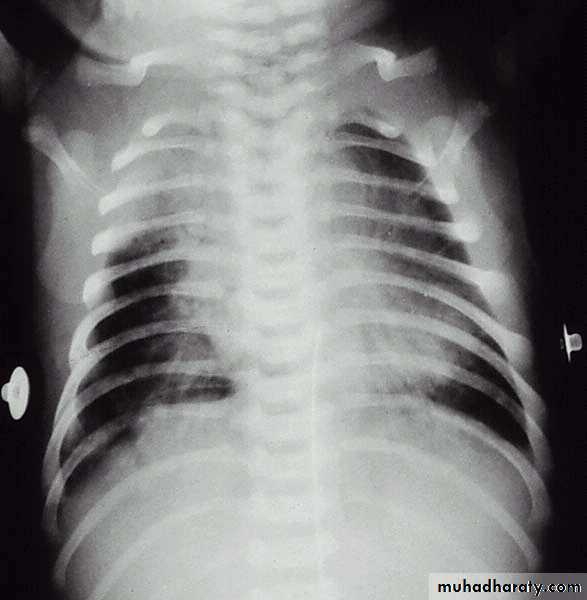

Chest x-ray:- Patchy infiltrates, overdistention , flattening of diaphragm, increase anteroposterior diameter& high incidence of pneumomediastinum& pneumothorax.

Meconium aspiration. The radiograph reveals irregularly distributed areas of hyperaeration and consolidation.